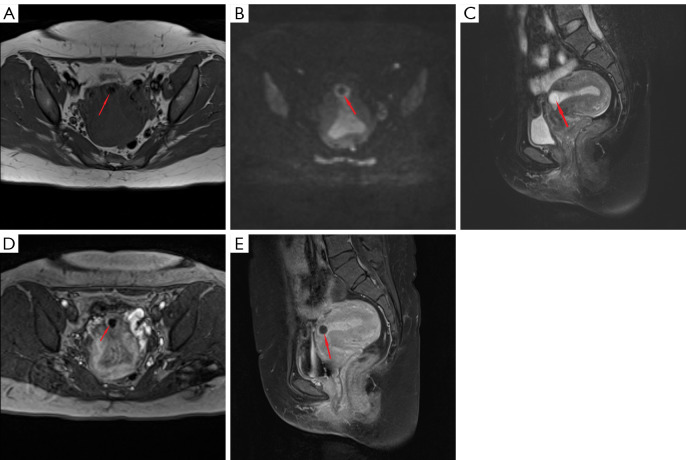

Results: Of the 80 cases confirmed by postoperative pathology, 67 (83.75%) were CSP. The area under the curve for the combinations C and D was larger (0.966 and 0.979, respectively) than that for combination A (0.883). The sensitivity, specificity, positive predictive value, and negative predictive value for combinations C and D were higher (combination C: sensitivity 98.51%, specificity 92.31%, positive predictive value 98.53%, and negative predictive value 92.31%; combination D: sensitivity 95.52%, specificity 92.31%, positive predictive value 98.46%, and negative predictive value 80.00%). The distribution of CSP type I (filled type), type II (partially filled type), and type III (covered type) was 19.40%, 59.70%, and 20.90%, respectively. There was no statistically significant difference in the length of the contact surface between the gestational sac and the scar among the MRI-type groups (H =0.012; P=0.994). However, the minimum thickness of the scar at the implantation site of type I was less than that in type II (H =-16.192; P=0.028), and the area of the gestational sac in the sagittal position was smaller in type I than in type III (H =-24.467; P=0.003).

Conclusions: The preferred MRI sequence combination for diagnosing CSP should be T2WI + DWI + DCE-MRI. MRI can effectively visualize the relationship between the gestational sac and the incisional diverticulum in CSP and facilitate imaging-based staging.